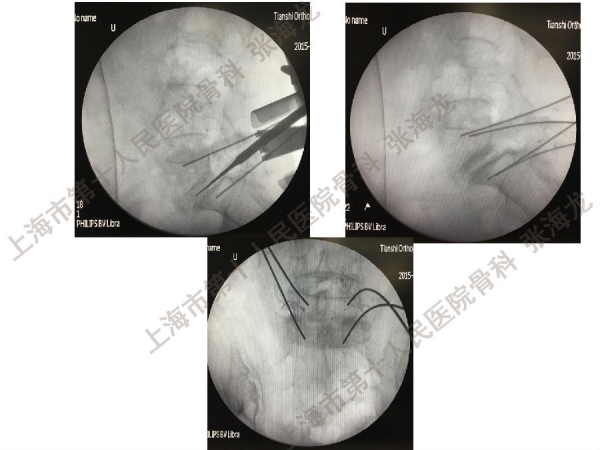

2008年3月至2010年8月,上海市第十人民医院骨科随访49例腰椎滑脱症(峡部裂型和退变型)患者,对比23例微创手术MIS-TLIF和26例开放手术治疗腰椎滑脱症的临床及影像学结果,进行了回顾性研究。

研究发现,Wiltse入路Mis-TLIF更直接的暴露峡部及关节突,对脊柱稳定性的影响较小;彻底松解辅助双重提拉复位Mis-TLIF,对于峡部裂型滑脱有较好的复位效果;对于峡部裂型滑脱,提拉复位在影像学参数上有一定优势;与原位融合相比,ODI.VAS.JOA无明显差异(样本量有限);对于退变性滑脱,单纯撑开椎间隙与原位融合可以获得较好疗效。